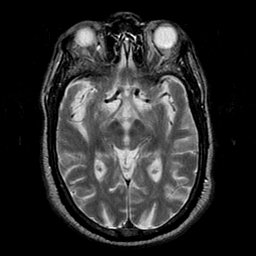

Subacute Stroke overlay -- Slice #10

[Home][Help][Clinical] Slice 10